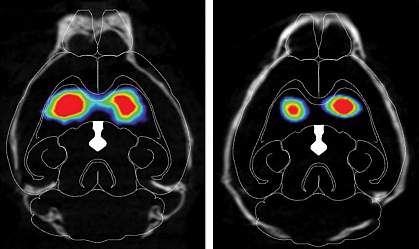

The researchers found that misfolded alpha-synuclein slowly spread to regions of the mouse brain associated with Parkinson’s disease, and dopamine-producing neurons started to die. The injected mice performed worse on tests of movement, dexterity, strength, memory, and mental health than mice that hadn’t received misfolded alpha-synuclein.

The scientists also found that interfering with the chain reaction caused by the misfolded protein stopped the spread of alpha-synuclein from gut to brain. Mice that had their vagus nerve cut before injection of the misfolded alpha-synuclein into their guts did not have the protein spread to their brains. Mice engineered not to produce any normal alpha-synuclein of their own also had no signs of the misfolded protein in their brains. Both these sets of mice performed similarly on all the tests to mice that didn’t receive any misfolded alpha-synuclein.